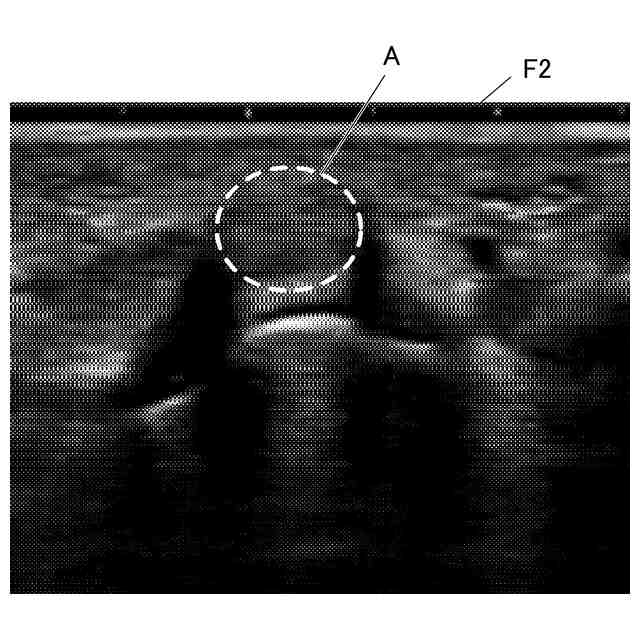

運動器及び麻酔領域の超音波検査では、筋、腱、神経束等の線維組織が撮像される。線維組織を撮像する場合には、超音波プローブを皮膚表面に押し当てた状態で超音波プローブの角度を変化させるあおり操作が行われる。あおり操作において、超音波プローブの線維組織に対する角度が適正でない場合、反射信号が得られない異方性反射組織となり、高輝度の超音波画像を得ることができない。

【解決手段】超音波診断装置は、被検体内に超音波を送信し、当該被検体内の対象組織で反射した超音波を受信して受信信号を得、当該受信信号に基づいて対象組織の超音波画像を出力する超音波診断装置であって、超音波プローブのあおり操作により当該超音波プローブの角度を変化させたときの複数のフレームの超音波画像を取得する取得部と、取得部により取得された複数のフレームから超音波プローブと対象組織とが直交する場合の超音波画像を含む基準フレームを抽出する抽出部と、抽出部により抽出された基準フレームを出力する出力部と、を備える。